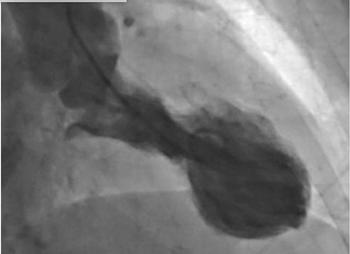

What is this seen post bypass surgery along the aorta?